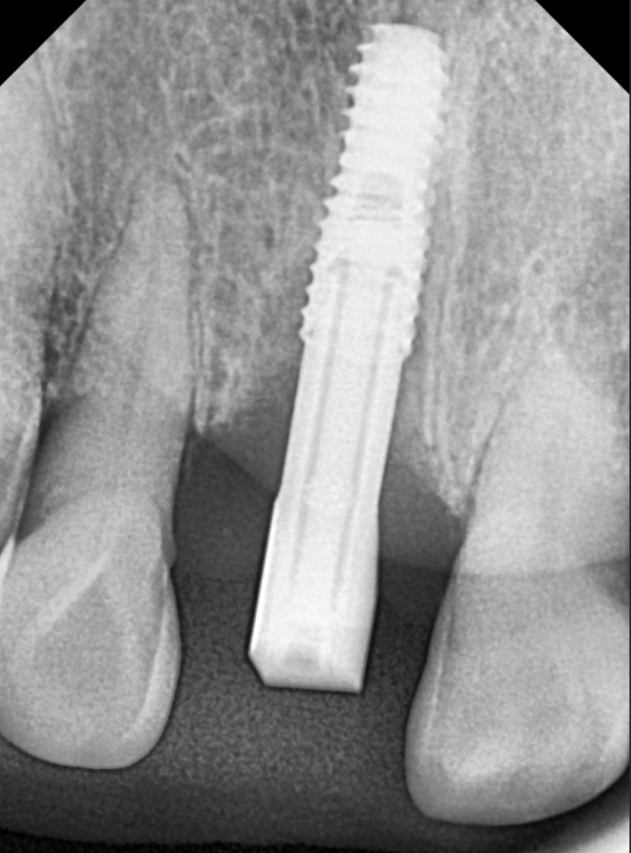

방사선 사진을 살펴보니,

옆 치아들에 비해 잇몸뼈가 많이

낮아진 걸 확인할 수 있었습니다.

더 자세히 살펴보기 위해

CT를 확인해 보았습니다.

CT 상에서 검게 투과되어 보이는 부분들이

모두 염증인데,

이미 치아를 지탱할 잇몸뼈가 상당 부분

녹아 없어진 상태네요..

특히 입천장 쪽 잇몸뼈가 소실되면서

치아를 받쳐주는 '지지대'가

아예 사라진 상황이었는데요,

결국 뿌리가 뼈에 간신히 걸쳐 있다 보니,,

치아는 앞쪽으로 뻗치면서

힘없이 아래로 내려앉을 수밖에 없겠죠.